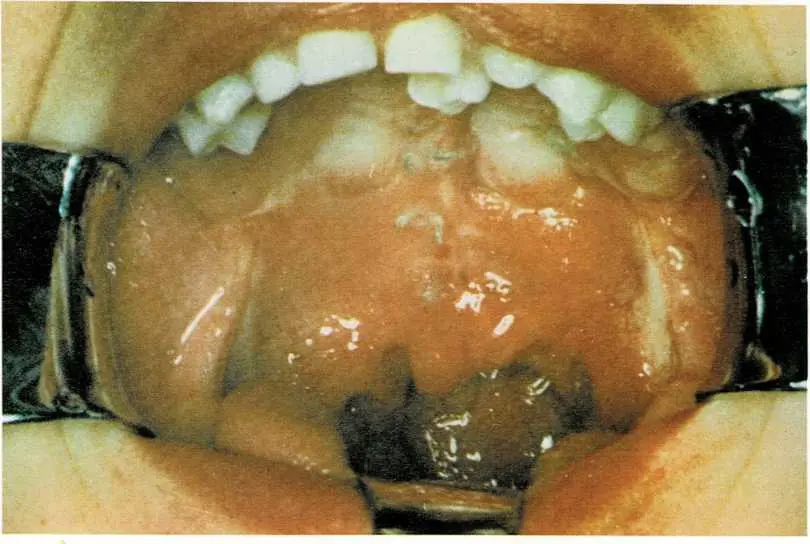

A cleft lip is a split in the child’s upper lip. It is present at

birth.

A cleft palate is a split in the palate (roof of the mouth). It is

present at birth.

Doctors sometimes use surgery to join the two parts of a cleft

palate.